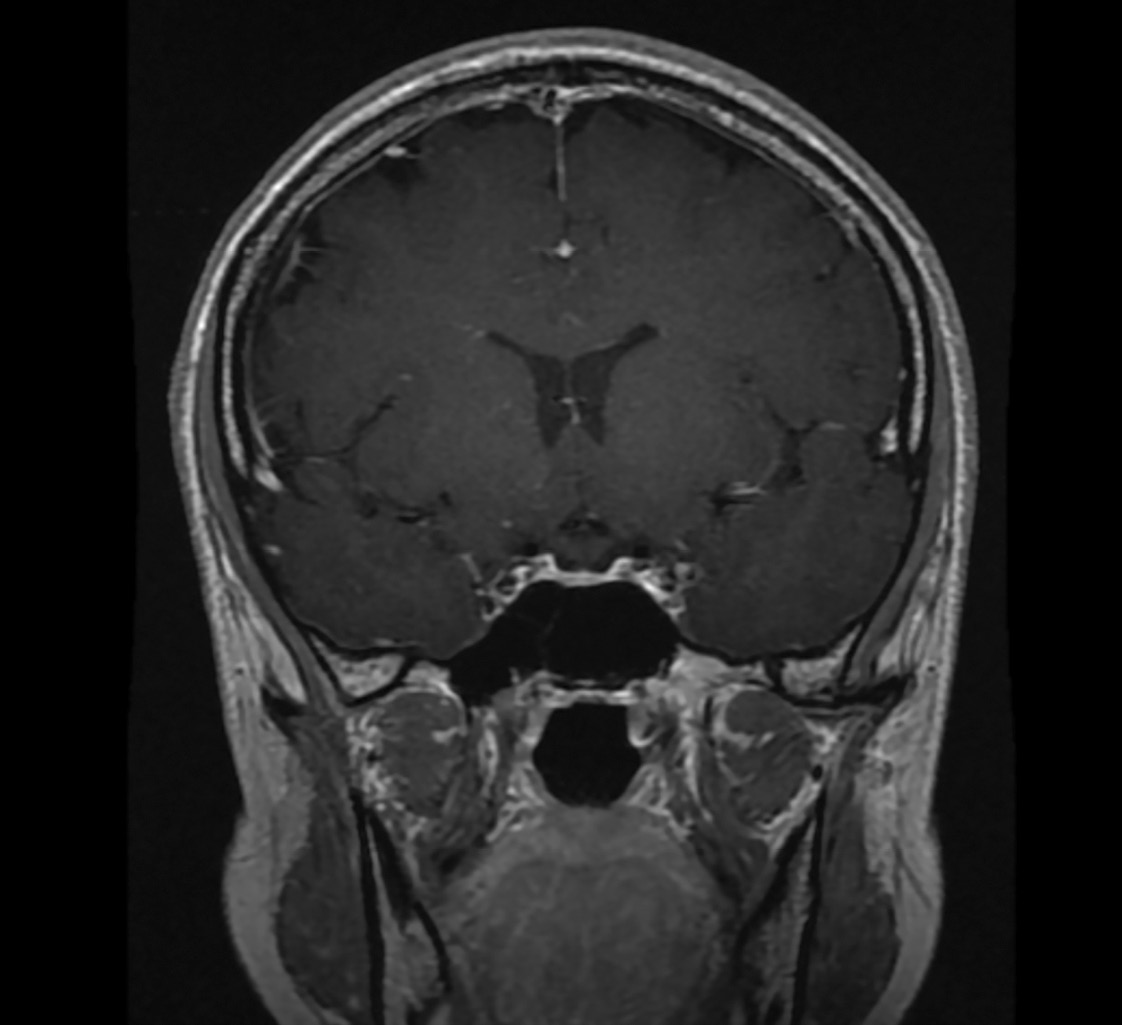

На фоне продолжающейся терапии дексаметазоном, по данным МРТ головного мозга, отмечался регресс изменений хиазмально-селлярной области с утолщением воронки гипофиза, отсутствием сигнала от нейрогипофиза (рис. 3, 4).

Рисунок 3. МРТ головы без контрастного усиления, Т2-взвешенное изображение,

коронарная (фронтальная) проекция. Сохраняется утолщение ножки гипофиза

(изменения указаны стрелкой).